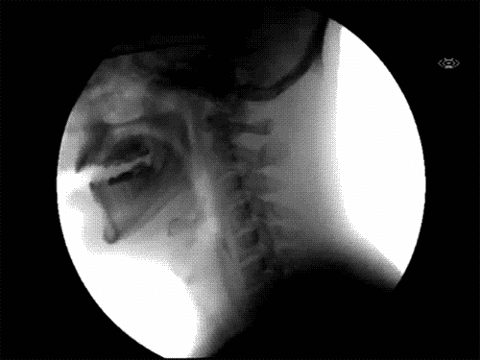

3. Chân đi giày cao gót

Các nhà khoa học Anh phát hiện ra rằng đi bộ thường xuyên trên giày cao gót dẫn đến sự méo mó của bàn chân, gây tổn thương dây chằng và khớp, dây thần kinh bị chèn ép. Chúng ta biết rằng muốn đẹp phải trả giá quá nhiều.